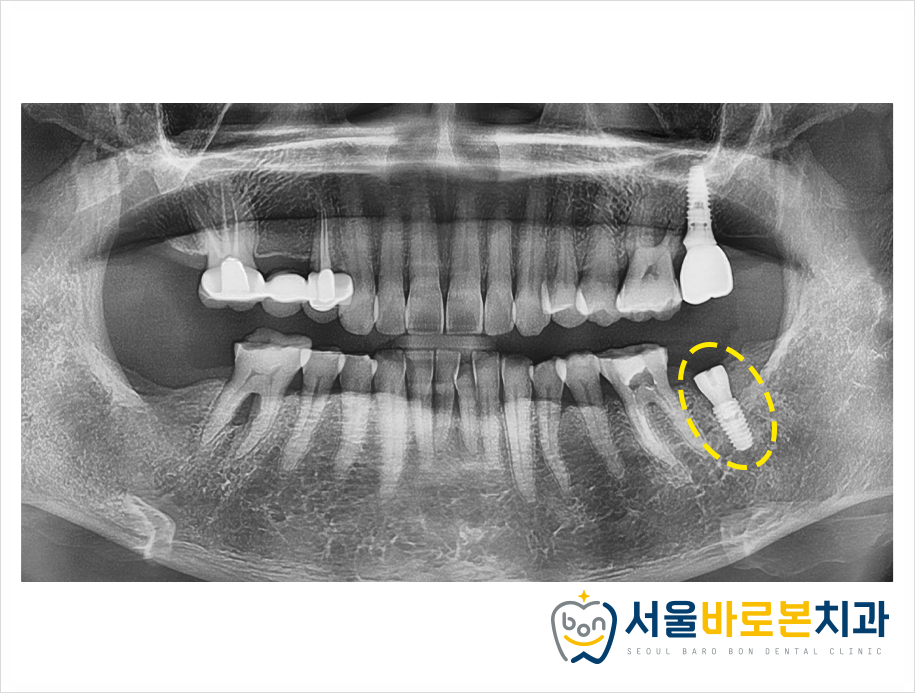

그러나 여전히 통증이 사라지지 않아

환자분과 상담을 진행한 후

앞쪽 치아는 신경치료를,

뒤쪽 치아는 발치 후 임플란트를

진행하기로 하였습니다!

염증이 있던 부위다 보니

잇몸뼈 흡수가 조금 있었는데,

염증 조직을 깨끗하게 긁어낸 후

뼈 이식까지 함께 진행하여

무사히 임플란트 식립을 도와드렸습니다.

신경치료도 뿌리 끝까지

깔끔하게 잘 이루어졌고,

임플란트도 남은 염증 조직 없이

잘 식립된 모습을 확인하실 수 있습니다!

추후 신경치료 한 치아는

크라운 보철물을 제작해서

치아머리 부분을 보호해 주고,

.

임플란트도 추후 본을 떠서 보철물을

제작해 드렸답니다!